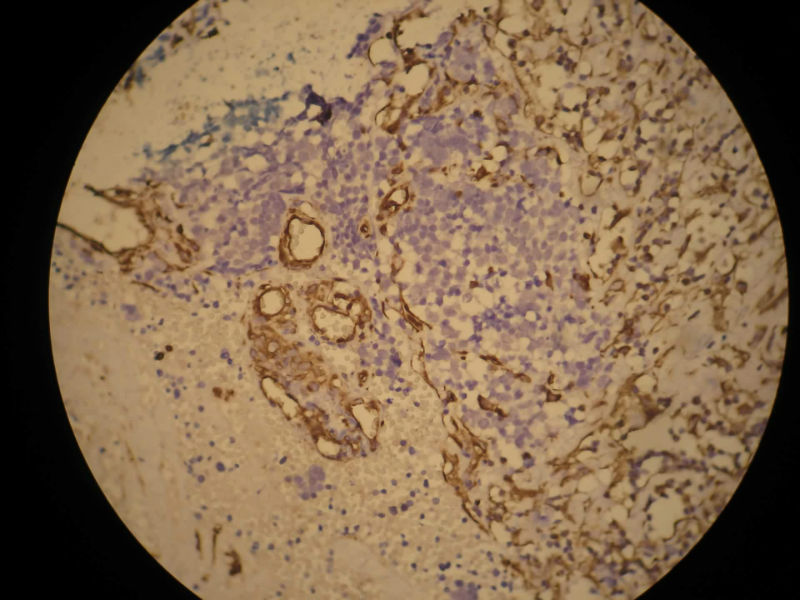

患者,M50Y,左侧肢体乏力半个月,肌力2级

MRI示右顶叶和小脑占位性病变,增强强化明显

术中见鱼肉样质脆,血管丰富,边界不清,部分囊性变,分块切除

大体:碎组织,4.2*3.5*2cm,呈鱼肉状,质嫩软。其间可见少量灰白组织,质韧。

Based on histology and immunohistochemistry, metastatic neuroendocrine carcinoma needs to be ruled out. I suggest TTF-1 stain. Also pay attention to nuclear morphology at high power view and see if it fits small cell carcinoma. It doesn't have to be a primary CNS tumor just because the border appears infiltrative.

谢谢Dr.mjma和楼上各位的指导。形态学符合小细胞癌。我们加做TTF-1,CD56和NSE,下周有结果。